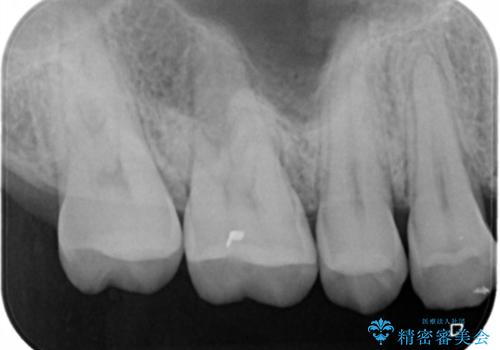

- 右上6番の虫歯治療を主訴に来院された患者様です。

切削量・形態を考慮し、セラミックインレーでの治療を計画しました。

保険の材料が劣化し中で虫歯が進行していたので、全て取り除いた上で形を整え型をとりインレーをセットしています。